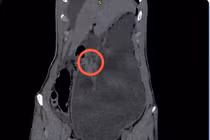

Theo đó, ngày 10/12/2025, bệnh nhân Đ.V.T, sinh năm 1927, trú tại TP Hải Phòng, nhập viện trong tình trạng vô cùng nguy kịch: đau bụng dữ dội vùng thượng vị, bụng chướng, khó thở, kèm theo nhiều bệnh lý nền nặng nề như viêm phổi, suy thận, suy kiệt tuổi già.

Bệnh nhân bị đau lưng do xẹp đốt sống, đã bơm xi măng được 4 ngày, bản thân có điện tim rung nhĩ, ngoại tâm thu thất. Với tuổi đời 98, tiên lượng ảnh hưởng đến tính mạng của bệnh nhân trong và sau phẫu thuật được đánh giá là có nguy cơ rất cao.

hang-vi.jpg

Bệnh nhân gần 100 tuổi nguy kịch do thủng dạ dày - Ảnh BVCC

Để chẩn đoán thủng dạ dày ở bệnh nhân thì có thể dựa trên các dấu hiệu lâm sàng hoặc thực hiện các chẩn đoán khác như chụp X-quang hay chụp CT scan bụng sẽ giúp xác định được lượng khí tự do ở trong ổ bụng.